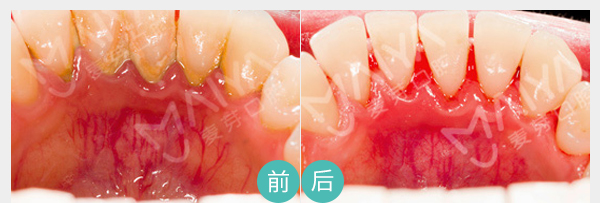

病变引起轻度松动

麦芽数字牙周治疗